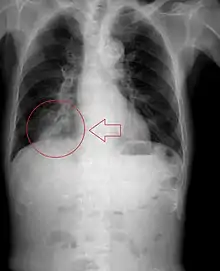

| Chest x-ray of a child after aspiration of a peanut: hyper-inflated left lung (right side of image) due to a valve mechanism of the peanut in the bronchus. | |

Radiography is the most common form of imaging used in the initial assessment of a foreign body presentation. Most patients receive a chest x-ray to determine the location of the foreign body.[2] Lateral neck, chest, and bilateral decubitus end-expiratory chest x-rays should be obtained in patients suspected of having aspirated a foreign body.[6] However, the presence of normal findings on chest radiography should not rule out foreign body aspiration as not all objects can be visualized.[2] In fact, up to 50% of cases can have normal findings on radiography.[7] This is because visibility of an object depends on many factors, such as the object's material, size, anatomic location and surrounding structures, as well as the patient's body habitus.[13] X-ray beams only show an object if that object's composition blocks the rays from traveling through, making it radiopaque and appearing lighter or white on the image. This also requires it to not be stuck behind something that blocks the beams first.[13] Objects that are radiopaque include items made of most metals except aluminum, bones except most fish bones, and glass. If the material does not block the x-ray beams it is considered radiolucent and will appear dark which prevents visualization.[13] This includes material such as most plastics, most fish bones, wood, and most aluminum objects.[13]

Signs on x-ray that are more commonly seen than the object itself and can be indicative of foreign body aspiration include visualization of the foreign body or hyperinflation of the affected lung.[13] Other x-ray findings that can be seen with foreign body aspiration include obstructive emphysema, atelectasis, and consolidation.[8]